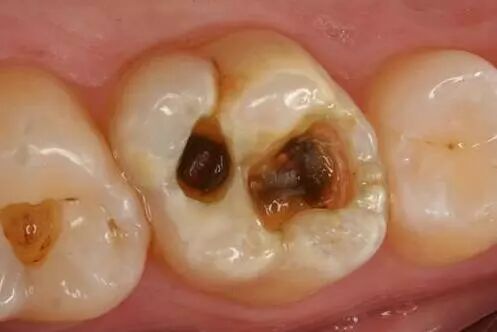

不知道大家有没有注意过,大牙上有时会有一些“小黑线”,面积不大,但是却让人心慌,所以这到底是蛀牙,还是沉淀?

小黑点分为两类,一类是色素在牙齿表面的沉淀,一类是牙齿病变而龋坏

如果是龋坏的话,情况可能会比较麻烦一点。由刚开始的小黑点,到侵犯牙釉质,再感染牙本质表层,引发牙髓炎,最后侵入牙根,牙齿不保。

小黑点最坏的后果是龋齿,龋齿的危害有多大?我们需要怎样进行治疗呢?